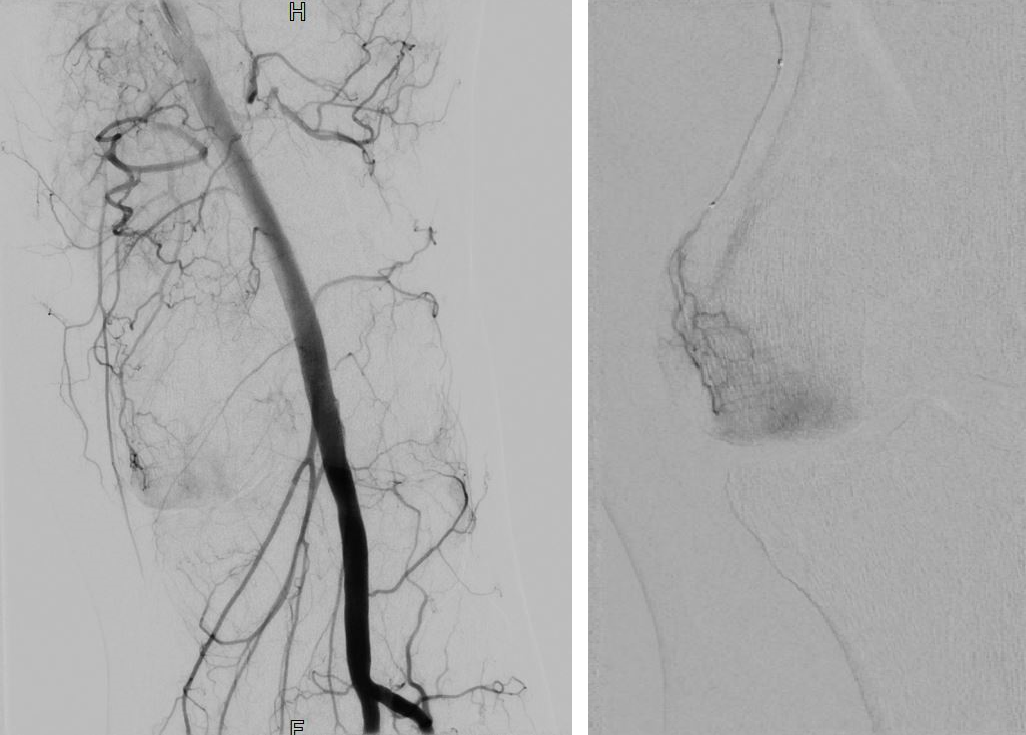

In der Radiologie erfolgt eine örtliche Betäubung der Leiste nach ausgiebiger Hautdesinfektion in Rückenlage auf dem Untersuchungstisch. Anschließend wird die Leistenschlagader punktiert und schmerzfrei mit dünnen Kathetermaterialien die entsprechenden feinen Zielgefäße unter Röntgenkontrolle im betroffenen Gelenk aufgesucht. Diese werden dann mit Imipenem/Cilastatin und gegebenenfalls zusätzlich mit Partikeln verschlossen (embolisiert), um so die Blutzufuhr zu den entzündeten Arealen zu unterbrechen. Je nach Anzahl der zu verschließenden Zielgefäße dauert der Eingriff in der Regel zwischen 45 und 90 Minuten. Am Ende des Eingriffs werden die Kathetermaterialien wieder vollständig entfernt, die Punktionsstelle in der Leiste abgedrückt und ein Druckverband angelegt.